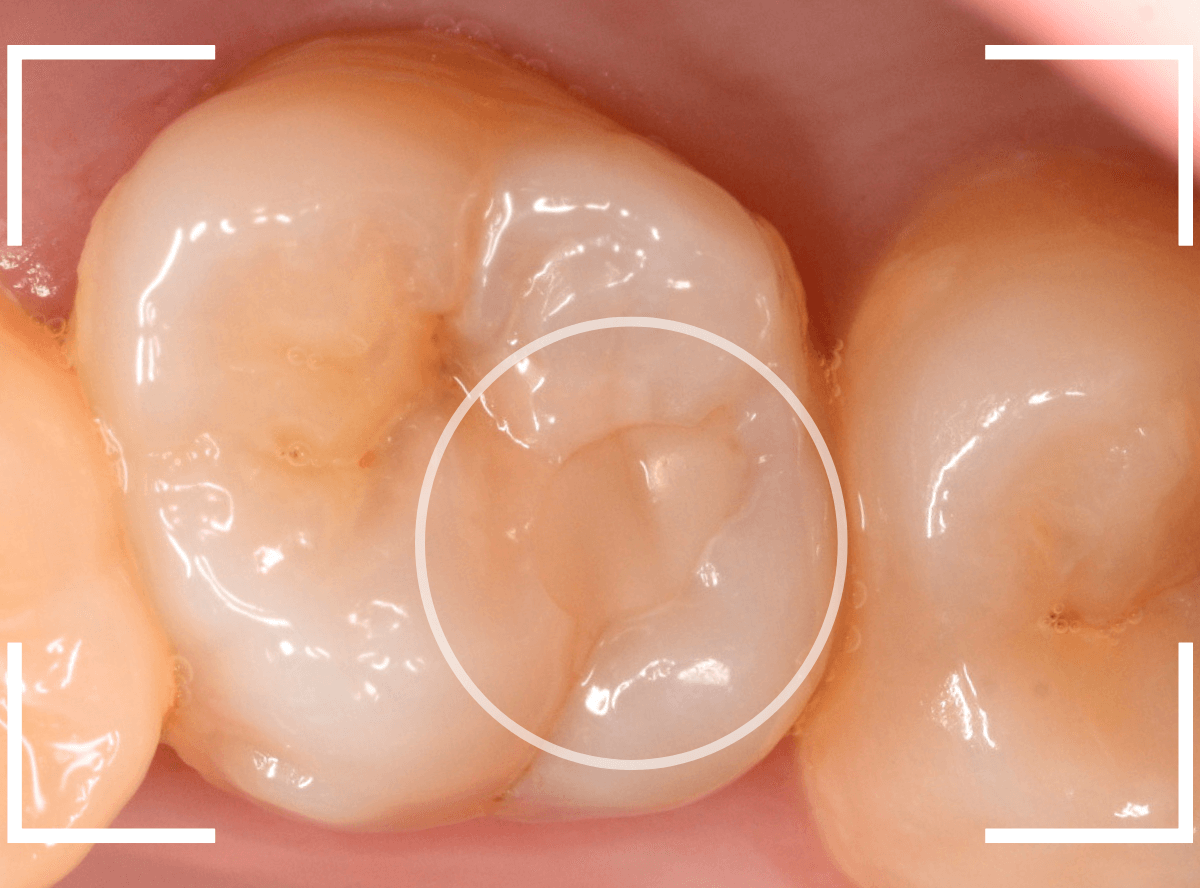

Case.13 問題なさそうなレジンの下で深い虫歯

他の歯の治療希望で来院された患者さんで、レントゲンで大きな虫歯が見つかった方です。

以前に虫歯を削って、レジンをつめる治療がしてあります。

表面を見る限り、特に問題はなさそうです。

レントゲン写真を撮影しました。

青い線が神経

黄色い線がレジン

赤い線が虫歯

です。

思ったよりも深い虫歯をレジンで埋めてあったようで、さらにその中が虫歯になっている状況です。

神経までかなり近い虫歯と思われます。

症状はありません。